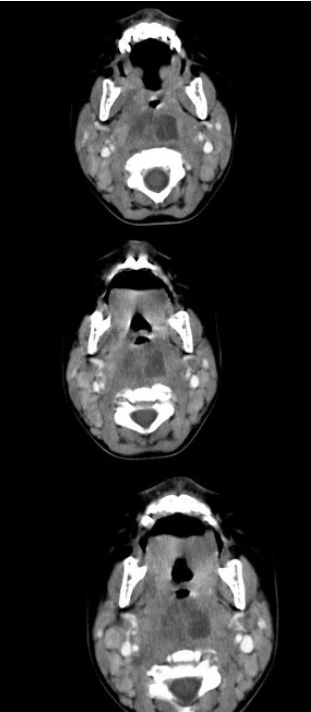

[多选题] 10个月大的婴儿,发热,曾患中耳炎,CT扫描如图所示,正确的描述或诊断是()A . 咽后壁软组织肿胀B . 其内密度不均C . 颈椎骨质未见明显异常D . 咽后壁脓肿E . 咽后壁寒性脓肿

[多选题] 10个月大的婴儿,发热,曾患中耳炎,CT扫描如图所示,请选择正确的描述或诊断()A . 咽后壁软组织肿胀B . 其内密度不均C . 颈椎骨质未见明显异常D . 考虑为咽后壁脓肿E . 考虑为咽后壁寒性脓肿